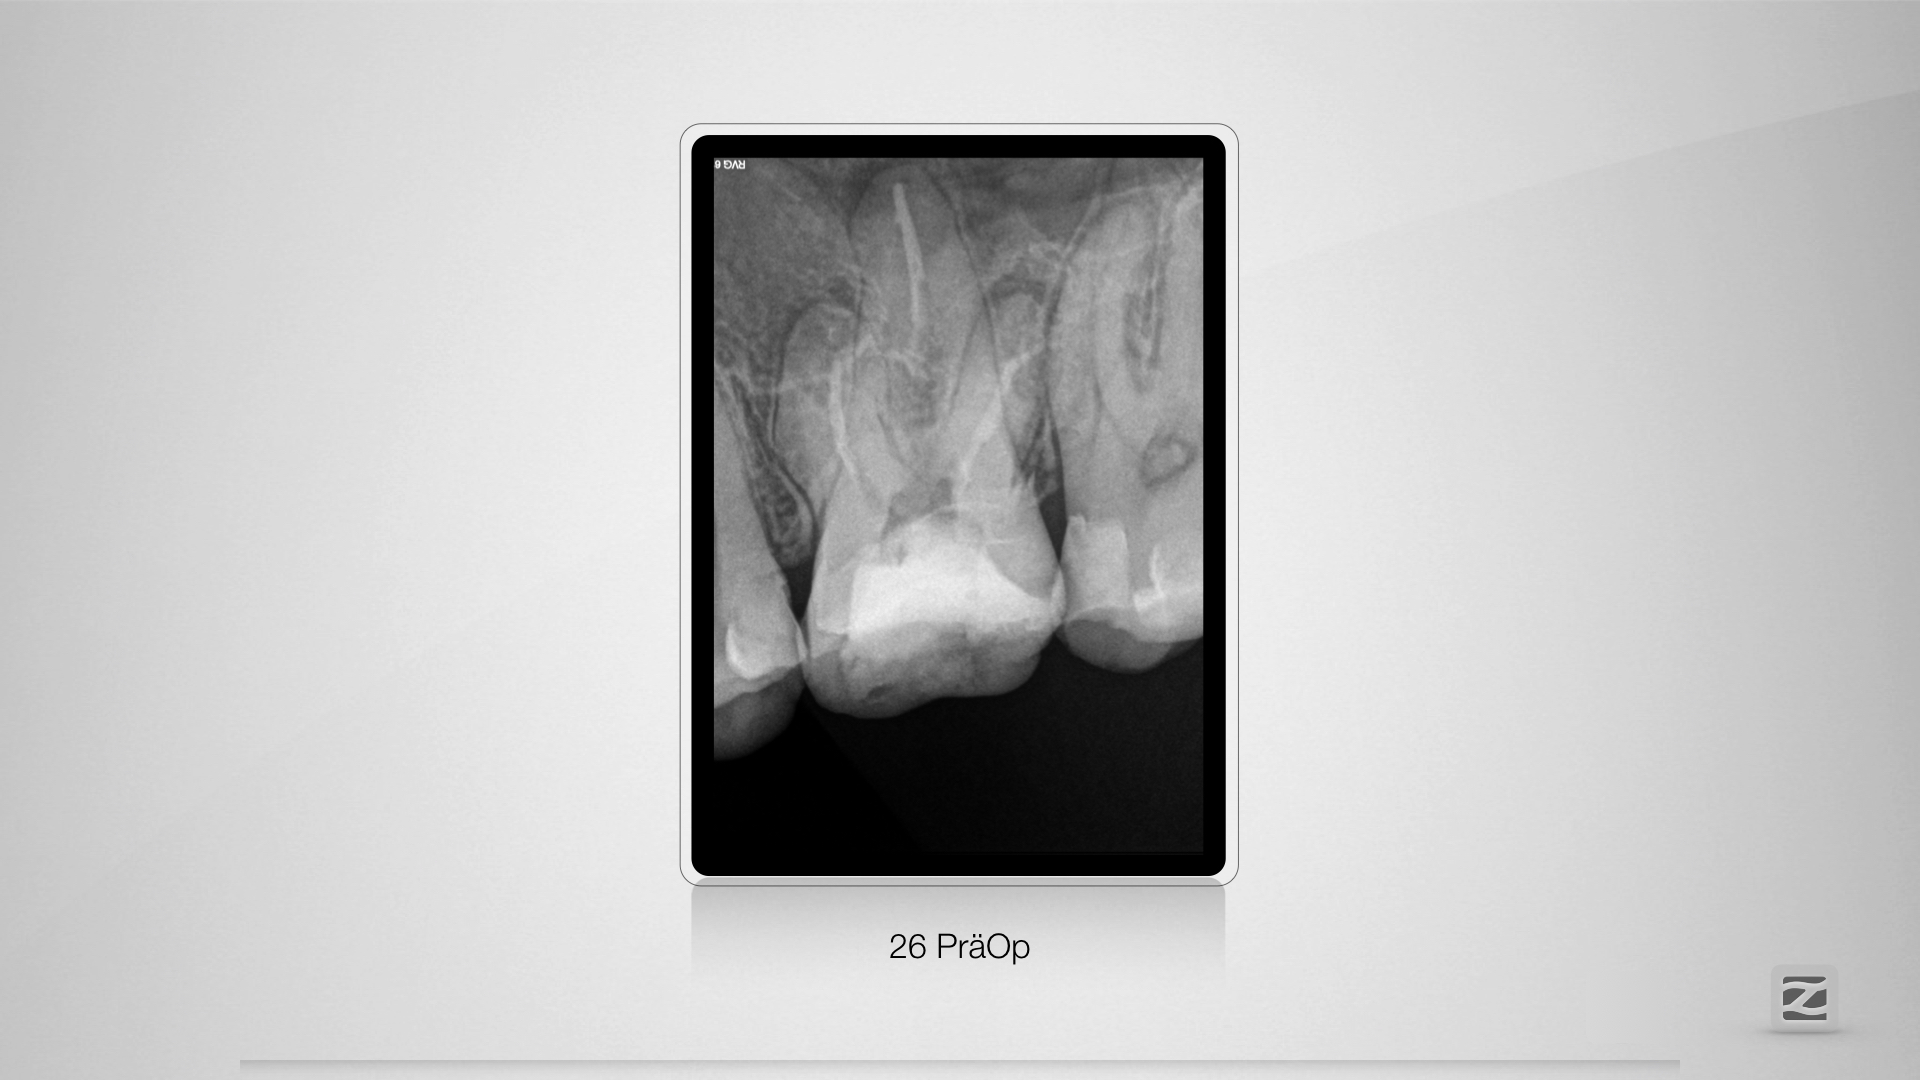

26D.001

Saving hopeless teeth